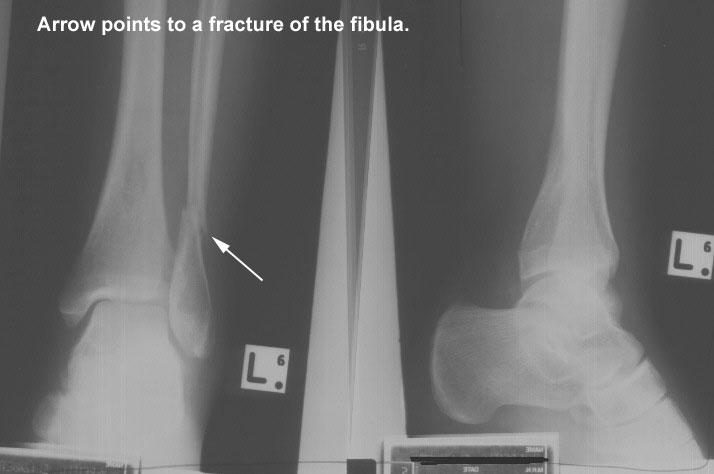

A 24-year-old football player was taken to the emergency room after receiving a blow to the left leg that resulted in severe pain and inability to stand up. The attending physician was able to locate a very painful area just below the knee and suspected a fracture to the fibula. He ordered a plain AP and lateral x-ray of the leg and knee. A clear spiral fracture in the left fibular neck and a cracked tibial shaft were shown on the x-ray. The patient was given analgesics, and a thorough neurological examination was done. No signs of nerve injury were detected. A plaster cast was applied, and the patient was discharged.